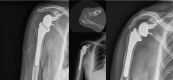

The reported rate of complications of reverse shoulder arthroplasty (RSA) seems to be higher than the complication rate of anatomical total shoulder arthroplasty.The reported overall complication rate of primary RSA is approximately 15%; when RSA is used in the revision setting, the complication rate may approach 40%.The most common complications of RSA include instability, infection, notching, loosening, nerve injury, acromial and scapular spine fractures, intra-operative fractures and component disengagement.Careful attention to implant design and surgical technique, including implantation of components in the correct version and height, selection of the best glenosphere-humeral bearing match, avoidance of impingement, and adequate management of the soft tissues will hopefully translate in a decreasing number of complications in the future. Cite this article: Barco R, Savvidou OD, Sperling JW, Sanchez-Sotelo J, Cofield RH. Complications in reverse shoulder arthroplasty. EFORT Open Rev 2016;1:72-80. DOI: 10.1302/2058-5241.1.160003.